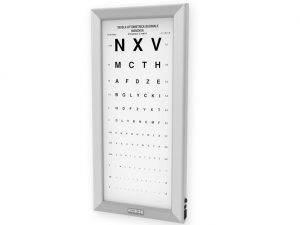

OTTOTIPO ULTRAPIATTO A LED – Monoyer

455,00 € (555,10 € IVA incl.) -

Tavole optometriche, Tavole optometriche a LED ultrapiatte